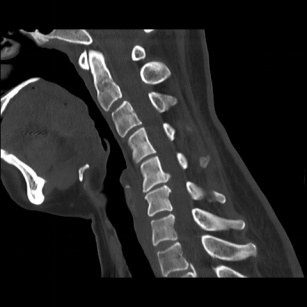

术前CT 术前MRI

近日,一名44岁女性患者由于近3个月来深受颈肩部不适困扰,同时伴有右上肢放射痛,严重影响日常生活,遂前往大场医院就诊。MRI检查结果显示:患者C56颈椎间盘突出,压迫脊髓及神经根,C5、C6锥体后缘骨赘增生,引发椎管狭窄。